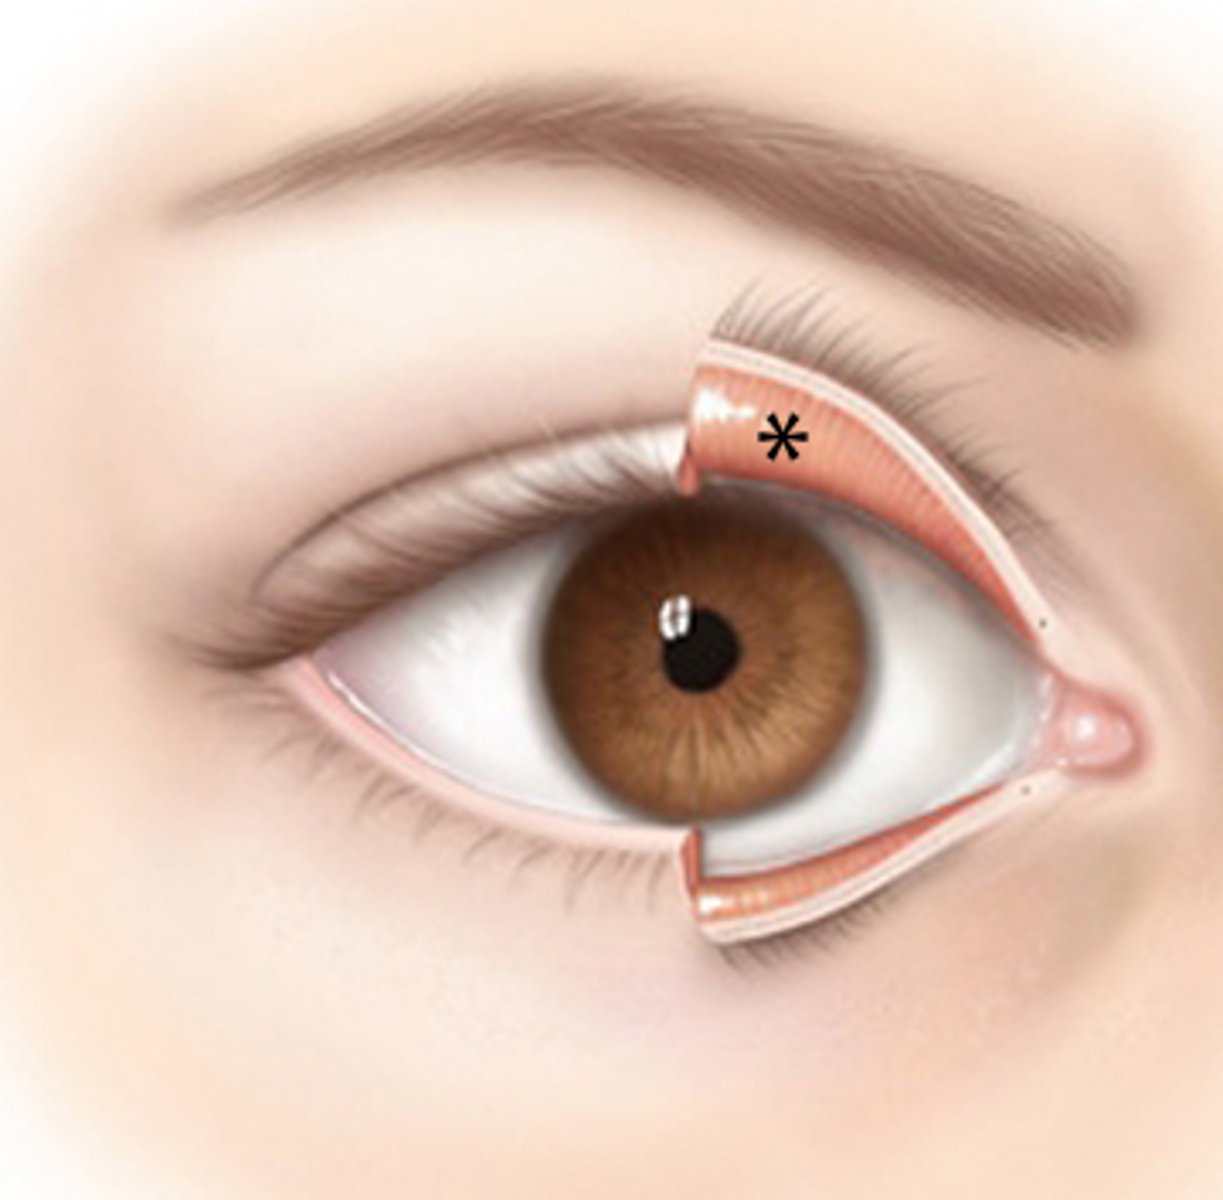

conjunctiva

nasolacrimal duct

lacrimal gland